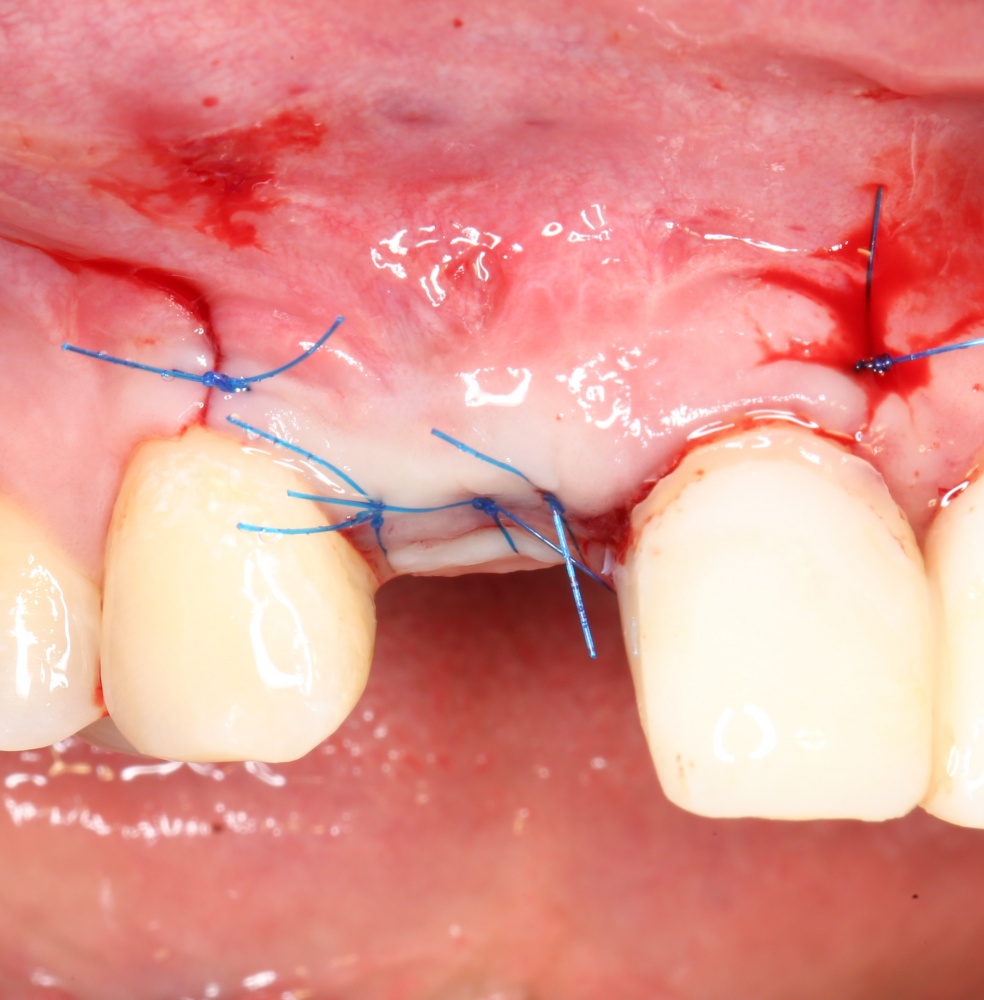

Наложение швов.

Если на этапе разреза и формирования раны всё сделано правильно, то наложение швов не вызывает особых трудностей. Периостотомия или послабляющие разрезы на периосте не требуются (ни практически никогда не требуются). А сами швы получаются аккуратными и герметичными:

Обрати внимание, что все шовные лигатуры находятся в пределах кератинизированной десны. Это позволяет избежать деформации тканей и лишних рубцов. В наиболее уязвимых местах (около зубов) шовные лигатуры лучше продублировать.

Если бы мне пришлось делать это сейчас, то я бы использовал непрерывный «матрацный» шов. Он удобнее, быстрее в наложении и комфортнее для пациента. Минус — если распускается, то распускается весь. К тому же, его очень неудобно снимать.

Несмотря на то, что уже тогда мы широко использовали непрерывные швы в подобных случаях, здесь я, во-первых, зассал (может распуститься), во-вторых, снятие швов предполагалось в поликлинике по месту жительства пациентки, и мне не хотелось, чтобы там при снятии швов начудили. Как выяснится позже — зря беспокоился.

Неизменно одно — в таких операциях мы использовали и до сих пор используем нерезорбируемые монофиламентные шовные материалы, поскольку они наиболее гигиеничные. Чтобы острые концы нитей не беспокоили пациента, их можно оплавить нагретой гладилкой или гуттаперчевым плаггером.